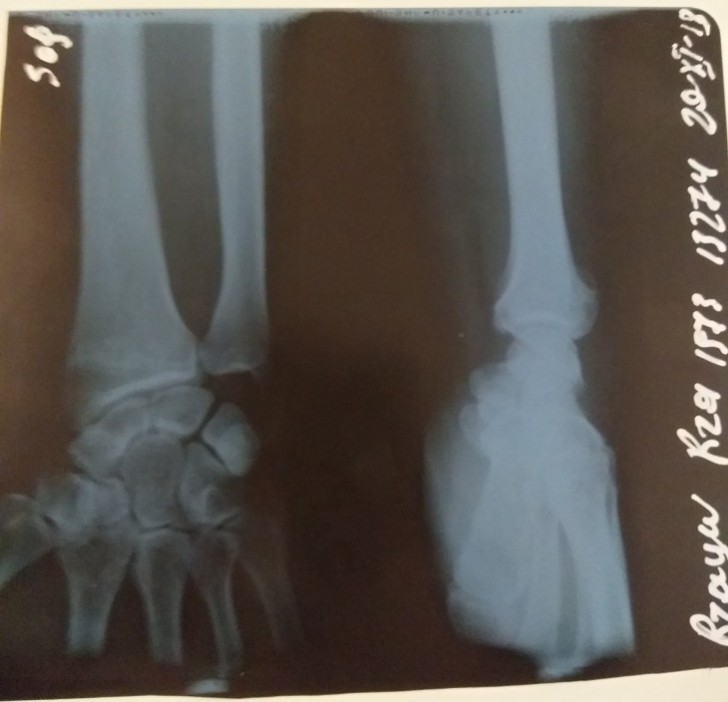

Qeyd edək ki, bir sıra KİV-lərdə guya təkcə T.Mirzəliyevin xəsarət alması haqda məlumat yayılıb. Lakin R.Rzayev də insident zamanı ağır xəsarət alıb. Onun sağ qolu biləkdən çatlayıb, sağ gözünün ətrafında xəsarət izləri var. Aktyorun qoluna 3 saylı Şəhər Klinik Xəstəxanasında gips qoyulub. R.Rzayev sabah tomoqrafiya olunması üçün başqa xəstəxanaya yaxınlaşacağını bildirib.